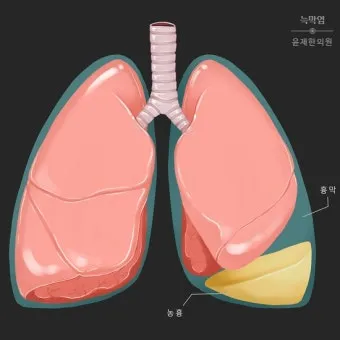

이 글에서 말하는 ‘폐에 물이 찼다’는 표현은 의학적으로는 흉수, 즉 폐를 둘러싼 흉막 사이 공간에 체액이 비정상적으로 많이 고인 상태를 뜻합니다.:contentReference[oaicite:0]{index=0}

가슴 안쪽에 5~10mL 정도의 액체는 원래 정상적으로 존재하지만, 200~300mL를 넘어서면서부터 X선이나 초음파에서 잘 보이고 500mL 이상이 되면 숨이 확연히 차기 시작하는 경우가 많다고 알려져 있지요.:contentReference[oaicite:1]{index=1}

흉막(가슴막)은 폐를 싸고 있는 두 겹의 막이고 그 사이 공간(흉강)에 소량의 액체가 있어야 폐가 부드럽게 움직이는데, 여기에 액체가 과도하게 고이면 흉수, 즉 폐에 물이 찬 상태가 됩니다.:contentReference[oaicite:3]{index=3}